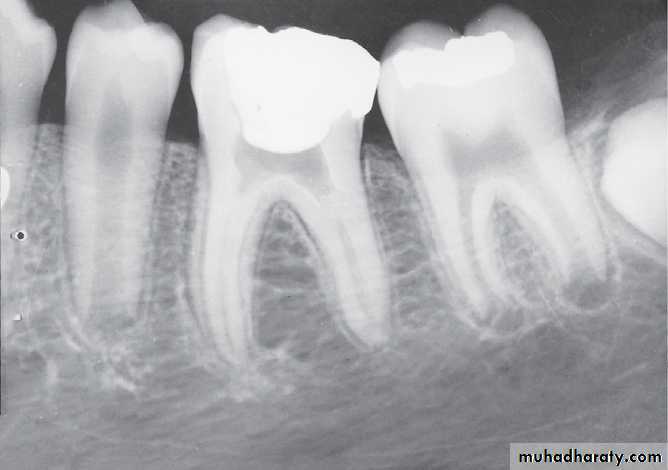

Patient’ age nearly 9 because the lower canines erupted and their eruption on 9-10 year and the upper lateral emerging now

This child is 7-8 years old because he has the upper maxillar centrals erupted (depending on schedule of time of eruption of permanent teeth (eruption lecture)